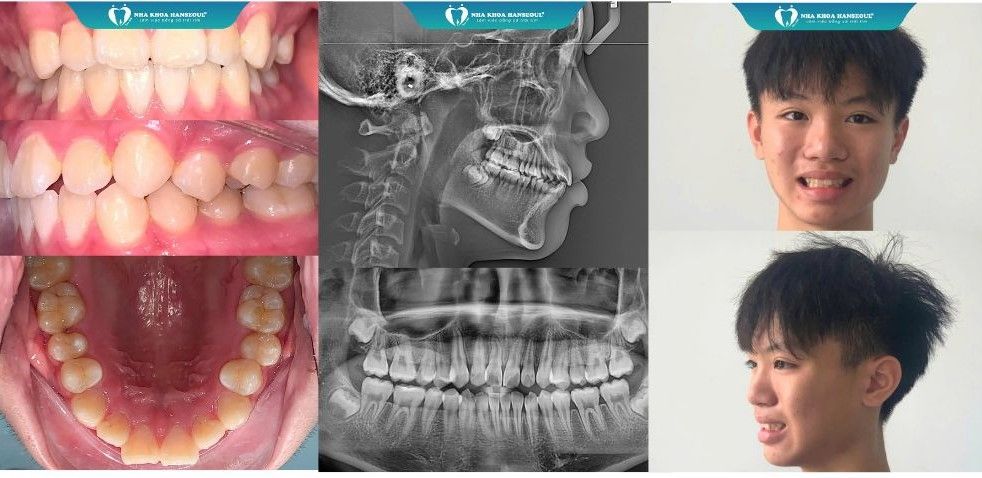

Bắt đầu hành trình

Ngày 20/10/2024 đánh dấu khởi đầu hành trình thay đổi nụ cười của Khánh Việt. Sau khi thăm khám, chụp phim và tư vấn chi tiết với bác sĩ Huyền – chuyên gia chỉnh nha tại Hanseoul, chị Huỳnh Hoa đã chọn phương pháp niềng Invisalign cho con mình, để con tự tin hơn khi đến trường. So với niềng răng mắc cài, niềng trong suốt giúp răng dịch chuyển hiệu quả, vẫn đảm bảo thẩm mỹ trong quá trình điều trị.

Kế hoạch niềng cá nhân hóa

Với công nghệ niềng răng hiện đại, độc quyền - Biosmart tại Hanseoul, bác sĩ Huyền lập kế hoạch dịch chuyển răng chi tiết, mô phỏng nụ cười sau niềng để Việt có thể thấy rõ lộ trình và kết quả.